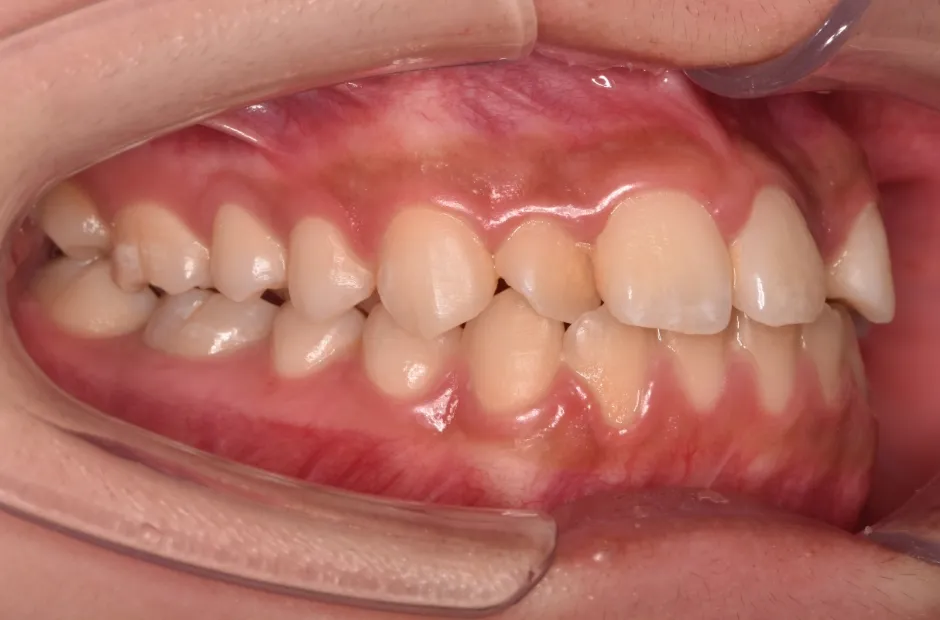

過剰歯

| 診断名・主訴 | でこぼこ |

|---|---|

| 年齢・性別 | 22歳・女性 |

| 治療期間・回数 | 1年6か月 |

| 治療に用いた主な装置 | リンガルブラケット |

| 抜歯部位 | 過剰歯 |

| 治療費 | 100万円(税抜) |

| リスク・副作用 | 装置による違和感・疼痛・歯肉退縮・歯根吸収・虫歯のリスクなど |

治療前